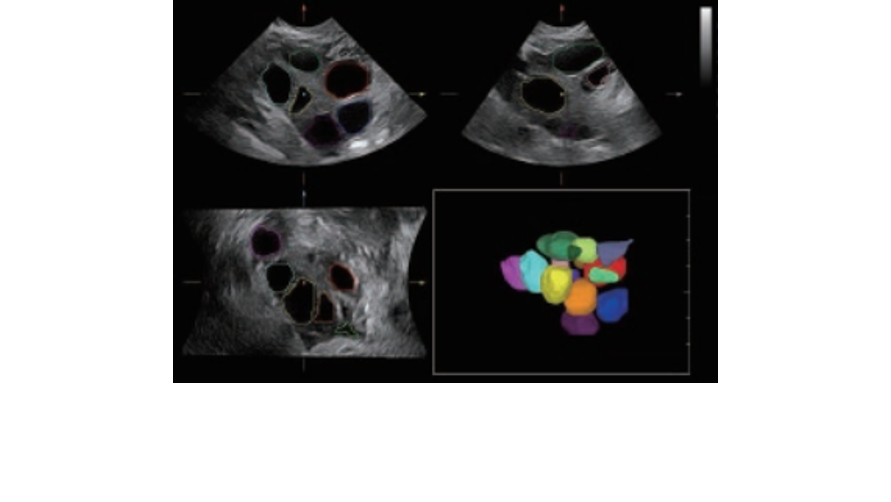

Fin dalla sua fondazione Mindray esplora continuamente nuovi modi per migliorare l'affidabilit├Ā diagnostica. Equipaggiata con la pi├╣ rivoluzionaria tecnologia ZONE Sonography?, la nuova piattaforma ZST+ di Resona 7 porta la qualit├Ā dell'immagine ecografica ad un livello superiore con l'acquisizione per zone e l'elaborazione dei dati canale.

Oltre alla qualit├Ā delle immagini di livello eccellente, Resona 7 migliora anche le capacit├Ā di ricerca clinica il rivoluzionario V Flow per la valutazione emodinamica vascolare, e l'acquisizione piani pi├╣ intelligente dal set di dati 3D per la diagnosi del sistema nervoso centrale fetale. Combinando il pi├╣ intuitivo funzionamento multi-touch basato su gesti e tutte le caratteristiche cliniche essenziali, Resona 7 sta veramente portando nuove tendenze nellŌĆÖinnovazione dellŌĆÖecografia.